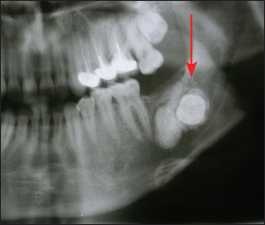

Impacted teeth located in edentulous areas and exhibiting pathological findings (Figure 10-3) should be removed, similar to retained roots. However, asymptomatic impacted teeth that are completely surrounded by bone may be retained—especially in older patients—in order to preserve arch morphology, provided that the patient is properly informed and the condition is monitored.